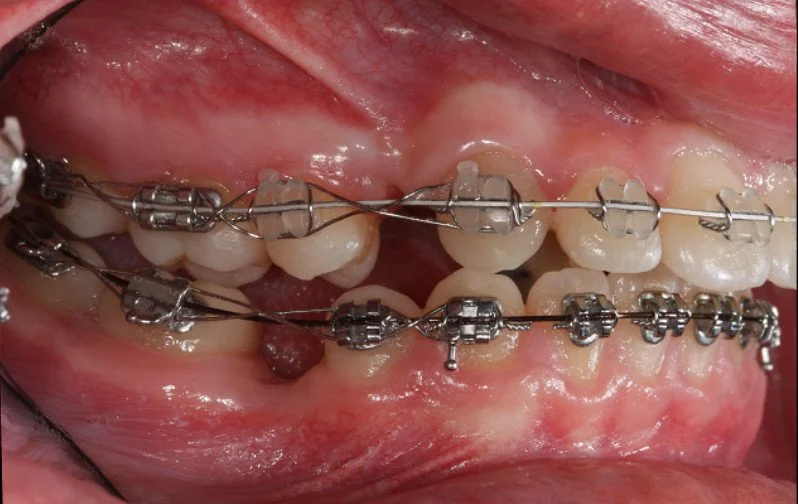

DURING

Trattamento con 4 estrazioni di una malocclusione di classe II con proclinazione degli incisivi superiori e inferiori.